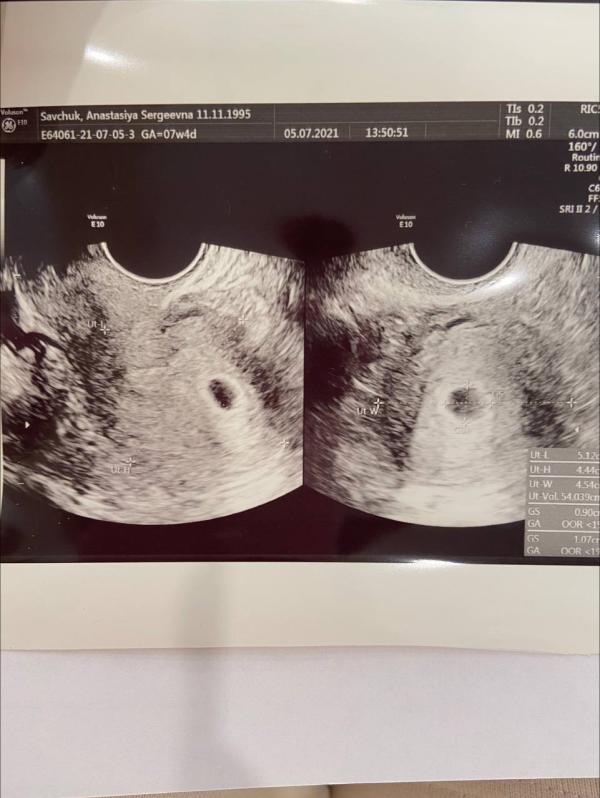

Я сходила на узи на 5 неделе, там тоже все было в рамках нормы: плодное яйцо в полости матки.